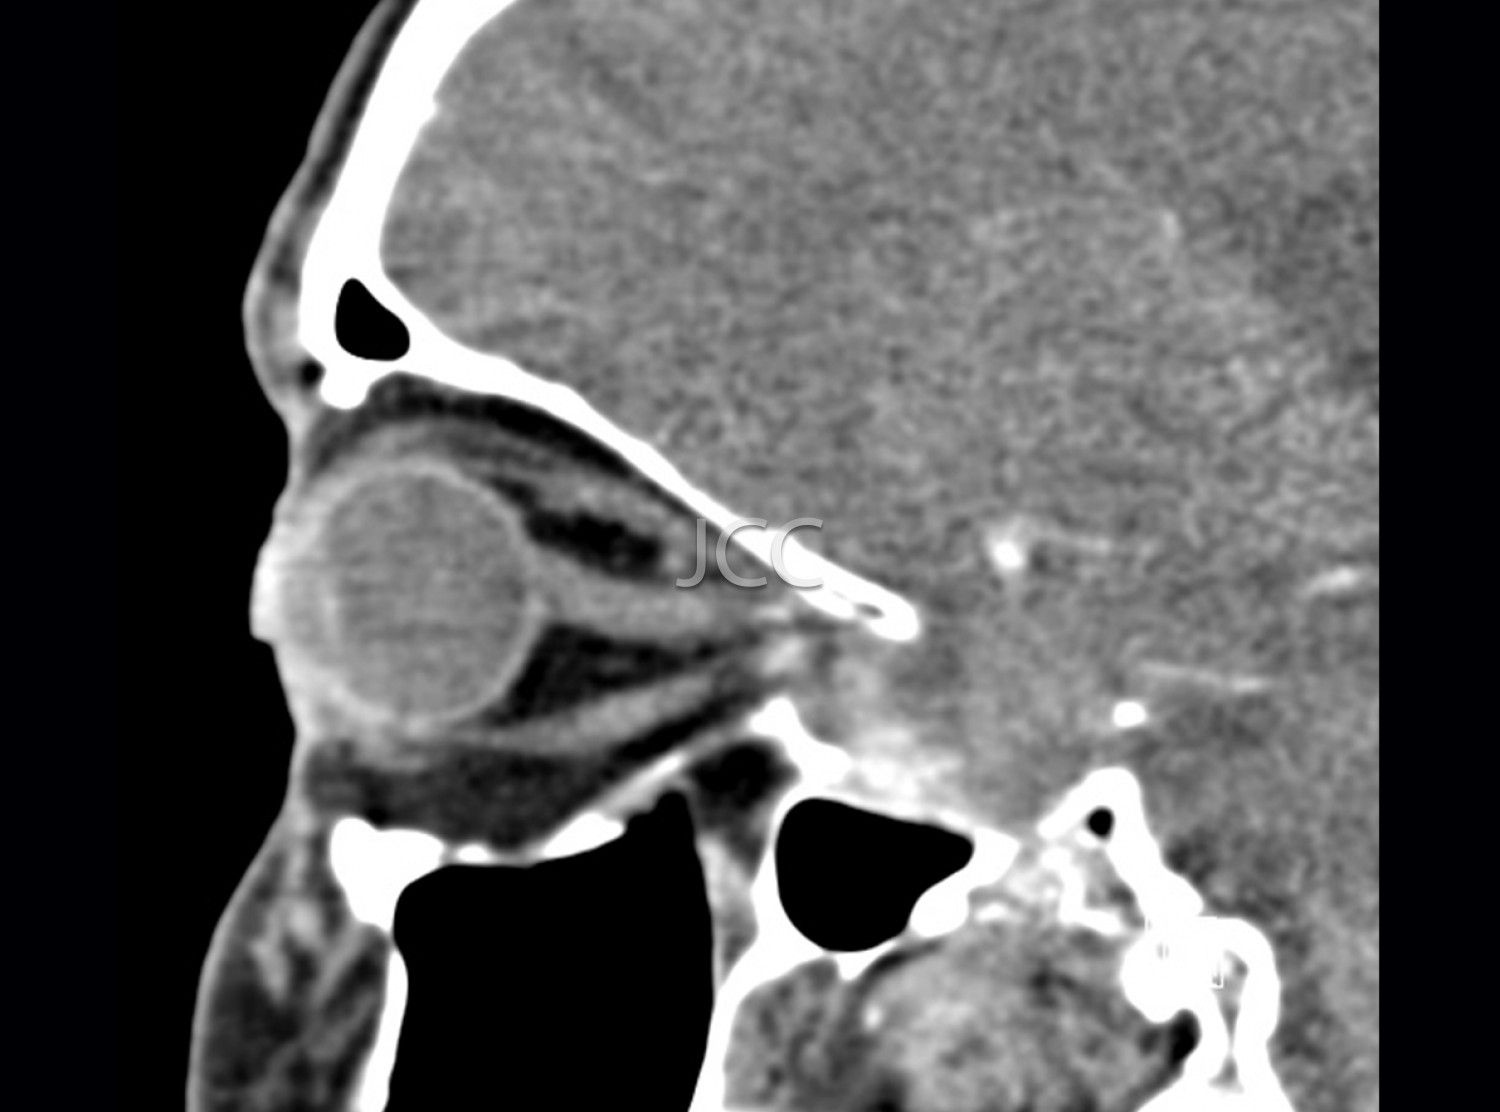

Computed Axial Tomography - Orbits CAT scan